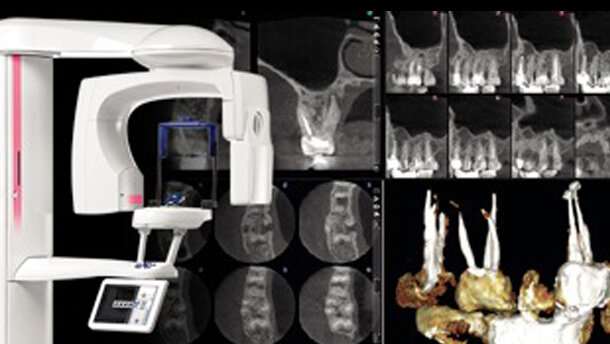

Planmeca introduce una nuova modalità di imaging che è appositamente progettata per gli studi di endodonzia. La nuova modalità di imaging è disponibile per tutte le unità della famiglia Planmeca ProMax 3D e fornisce una perfetta visualizzazione anche dei minimi dettagli anatomici.

La nuova modalità di imaging è ideale sia per endodonzia sia per casi con piccoli dettagli anatomici, come l'imaging dell'orecchio. Il programma produce immagini ad altissima risoluzione con una dimensione molto piccola del voxel (solo 75 micron). Grazie agli intelligenti Planmeca AINO filtro rimozione del rumore e Planmeca ARA algoritmo di rimozione artefatto, vengono prodotte immagini cristalline e senza rumore.

Ricostruzioni in metallo o otturazioni delle radici presenti nella bocca del paziente possono causare ombre e striature nelle immagini CBCT. L' intelligente Planmeca ARA Artefact Removal Algorithm elimina questi artefatti efficacemente dalle immagini Planmeca ProMax 3D.

Una dose particolarmente bassa di radiazioni o un voxel di piccola dimensioni possono causare disturbi nelle immagini radiografiche 3D. Il nuovo Planmeca Aino Adaptive Image Noise Optimiser è un filtro intelligente che riduce il rumore nelle immagini CBCT senza perdere dettagli importanti. Il filtro migliora la qualità dell'immagine nella modalità endodonzia, dove il rumore è innato a causa della dimensioni estremamente ridotte del voxel.

Planmeca AINO permette anche di ridurre i valori di esposizione e di conseguenza la dose di radiazioni in tutte le altre modalità di imaging. E' particolarmente utile quando si utilizza il nuovo protocollo Planmeca Ultra Low Dose nelle unità Planmeca ProMax 3D. Il pionieristico protocollo Ultra Low Dose permette l'imaging CBCT con una dose ancora più bassa rispetto all'imaging panoramico 2D tradizionale offrendo così una grande quantità di informazioni anatomiche dettagliate a una dose molto bassa per il paziente. Immagini Ultra Low Dose sono ideali per numerosi casi clinici, come post-operatorio e studi di follow-up, ortodonzia, studi ORL e pianificazione degli impianti.